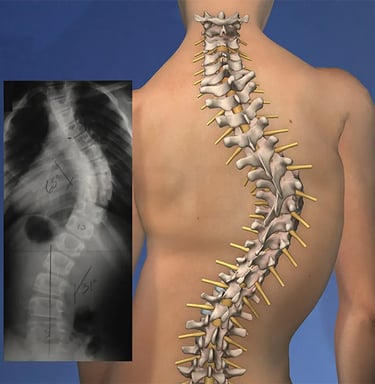

La escoliosis es una condición en la que la columna vertebral se curva de manera anormal, a menudo formando una "S" o una "C" en lugar de estar recta. Aunque algunos casos de escoliosis son leves y no causan problemas significativos, otros pueden generar dolor, incomodidad e incluso dificultar el movimiento y la postura. Comprender los síntomas, las causas y los tratamientos disponibles para la escoliosis es esencial para gestionar esta condición y mejorar la calidad de vida.

La escoliosis es una condición caracterizada por una curva anormal en la columna vertebral, que puede ocurrir a cualquier edad, pero se diagnostica comúnmente durante la niñez o la adolescencia. La curvatura puede variar desde leve hasta severa y generalmente se desarrolla a medida que la columna crece. En algunos casos, la escoliosis puede empeorar con el tiempo, lo que provoca más incomodidad, restricción de movimiento y, en casos graves, problemas respiratorios.